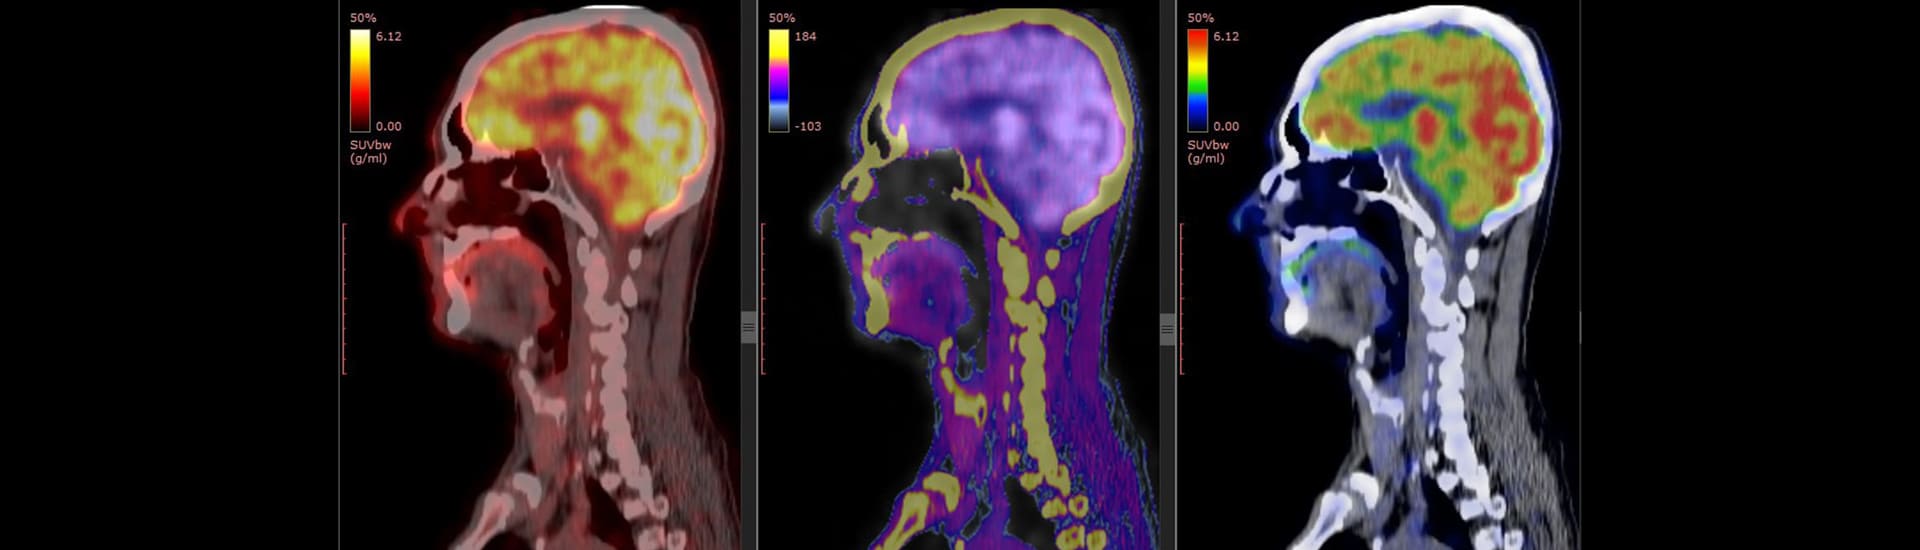

Brain Scans

Brain scans include several types of imaging techniques used to diagnose tumors, blood vessel malformations, stroke, injuries, abnormal brain development, and hemorrhage in the brain. Types of brain scans include computed tomography (CT), magnetic resonance imaging (MRI), and single proton emission (SPECT) scans.

• Positron emission tomography (PET) scans provide two- and three-dimensional pictures of brain activity by measuring radioactive isotopes that are injected into the bloodstream. PET scans of the brain are used to detect or highlight tumors and diseased tissue, show blood flow, and measure cellular and/or tissue metabolism. PET scans can be used to evaluate people who have epilepsy or certain memory disorders, and to show brain changes following injury. PET may be ordered as a follow-up to a CT or MRI scan to give the physician a greater understanding of specific areas of the brain that may be involved with problems. PET scans are performed by skilled technicians at highly sophisticated medical facilities in a hospital or at an outpatient testing facility. A low-level radioactive isotope, also called a tracer, is injected into the bloodstream and the tracer’s uptake in the brain is measured. The person lies still while overhead sensors detect gamma rays in the body’s tissues. A computer processes the information and displays it on a video monitor or on film. Using different compounds, more than one brain function can be traced simultaneously. PET is painless and uses small amounts of radioactivity. The length of test time depends on the part of the body to be scanned.

• Single photon emission computed tomography (SPECT) is a nuclear imaging test that can be used to evaluate certain brain functions. A SPECT scan may be ordered as a follow-up to an MRI to diagnose tumors, infections, brain regions involved in seizures, degenerative spine disease, and stress fractures. A dopamine transporter imaging with single-photon emission computed tomography (DaT-SPECT) scan can be used to help diagnose Parkinson disease. During a SPECT scan, the person lies on a table while a gamma camera rotates around the head and records where the radioisotope has traveled. That information is converted by computer into cross-sectional slices that are stacked to produce a detailed three-dimensional image of tracer within the brain. The test is performed at either an outpatient imaging center or a hospital.